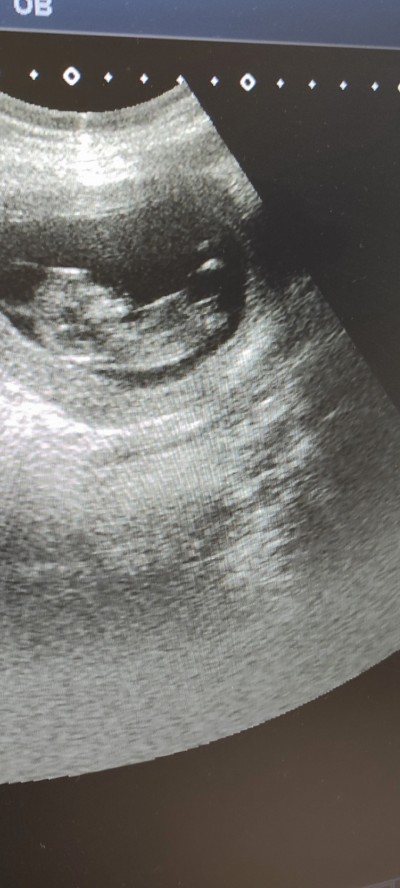

Yine ben yine cinsiyet tahmini belki başka hanımlar denk gelir beni bilmeyen ümidiyle :)))(

Bana kız gibi geldi

Kız bence kesesi yuvarlak

Cıktısı var erkek bu

Kızdada oluyo nuba göre kız aşşağı doğru uzun ama okadar ınsan var bi anlayamadılar hahshshw:)))

Kız sanki:)))

Kız gibi kaç haftalık

11 hftalık

Aslında 14 haftalık gittiğimde %90 kız dedi tekrar 16 haftalık gittim kıza benzşyo dedi baska doktor en son gittiğim söylemedi  değişimi acaba baskamresmimde yok elimde devlet hastahanesi oldugu için

Walla bana erkek geldi öyle hissettim öğrenince yaz post aç :)

Banada erkek gibi geldi